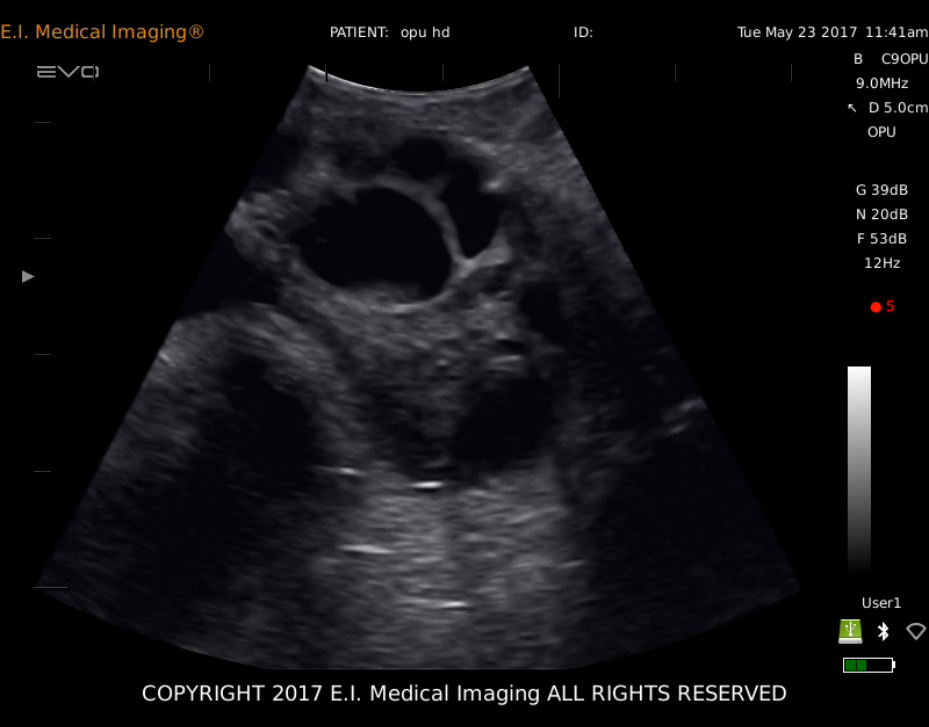

产品影像图

• 牛卵巢卵泡

2、操作人员一手拿探头一手通过直肠对卵巢进行牵引,把卵巢牵引到贴在探头上,使得我们能在EVO显示屏上清楚的看到卵巢,根据图像区分卵泡和CL,调整B超探头和卵巢的位置使监视器上卵泡位于穿刺针直线的延长线上时,推进穿刺针对卵泡进行穿刺.同时,用脚踏开关控制真空泵抽取卵泡液,真空泵的压力在60~80mm汞柱之间调整。

3、从监视器上可以观察到被抽取卵泡液和卵泡开始缩小,变得不规则,黑色的影像变成了亮片,直到卵泡在图像上消失,退出穿刺针,再对第二个卵泡进行穿刺,抽取卵泡液,直到该侧卵巢上2ram以上的卵泡被穿刺完后,调整探头以相同的方法对另一侧卵巢的卵泡进行穿刺。最后,所有符合条件的卵泡都被穿刺完后,用含有肝素的PBS液冲洗采卵针及导管,冲洗液也方入收集管。